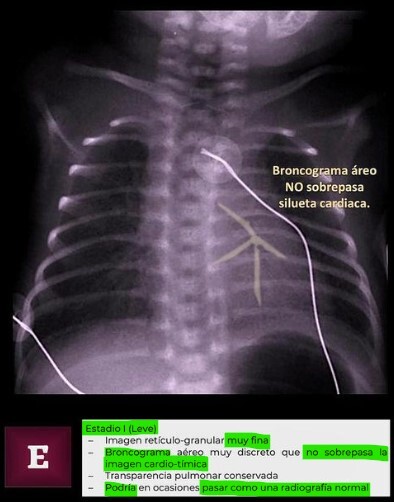

Q

SDR Estadio l

A

• Broncograma no sobrepasa silueta cardíaca